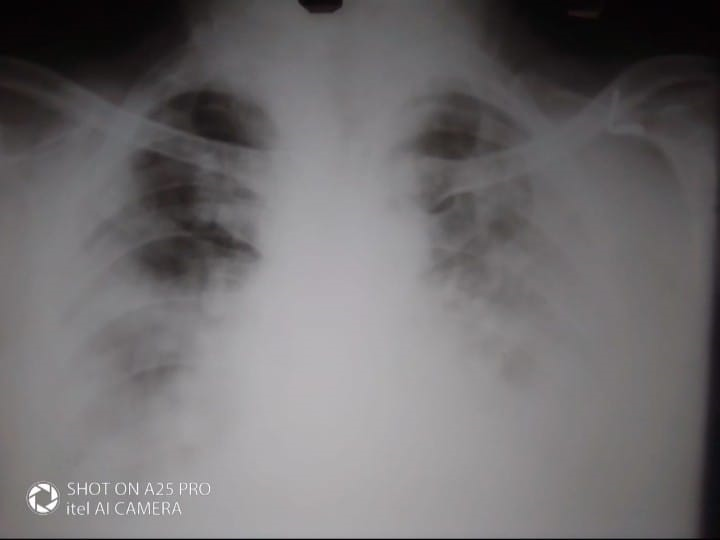

A 54 year old man is brought to ED by his 2 sons with complaints of increasing drowsiness , distress and confusion.

They also bring a chest X ray done 1 day ago. According to his son , he has been unwell since 4 days but they provided him treatment at home.

Severe Acute Respiratory Distress Syndrome secindary to Covid 19 Pneumonitis